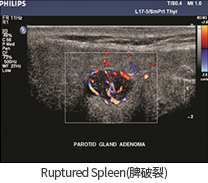

• Ruptured Spleen(비장파열)

• Parotid Gland Adenoma(이하선종)